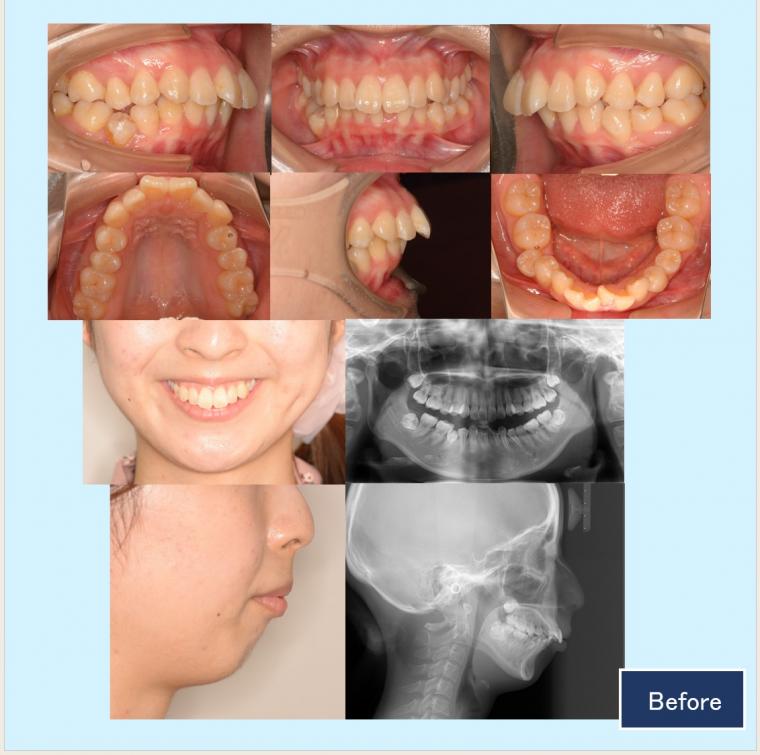

No.52 口ゴボと下顎後退症をハーフリンガルで改善した症例

20代女性 千葉市花見区

『あごなし、ガミースマイルを外科矯正は避けてできる限り治したい。口ゴボで、口を閉じることができない』という主訴でした。

診断名:口唇閉鎖不全伴う下顎後退症

年齢:20代 治療期間:2年3ヵ月 治療回数:28回